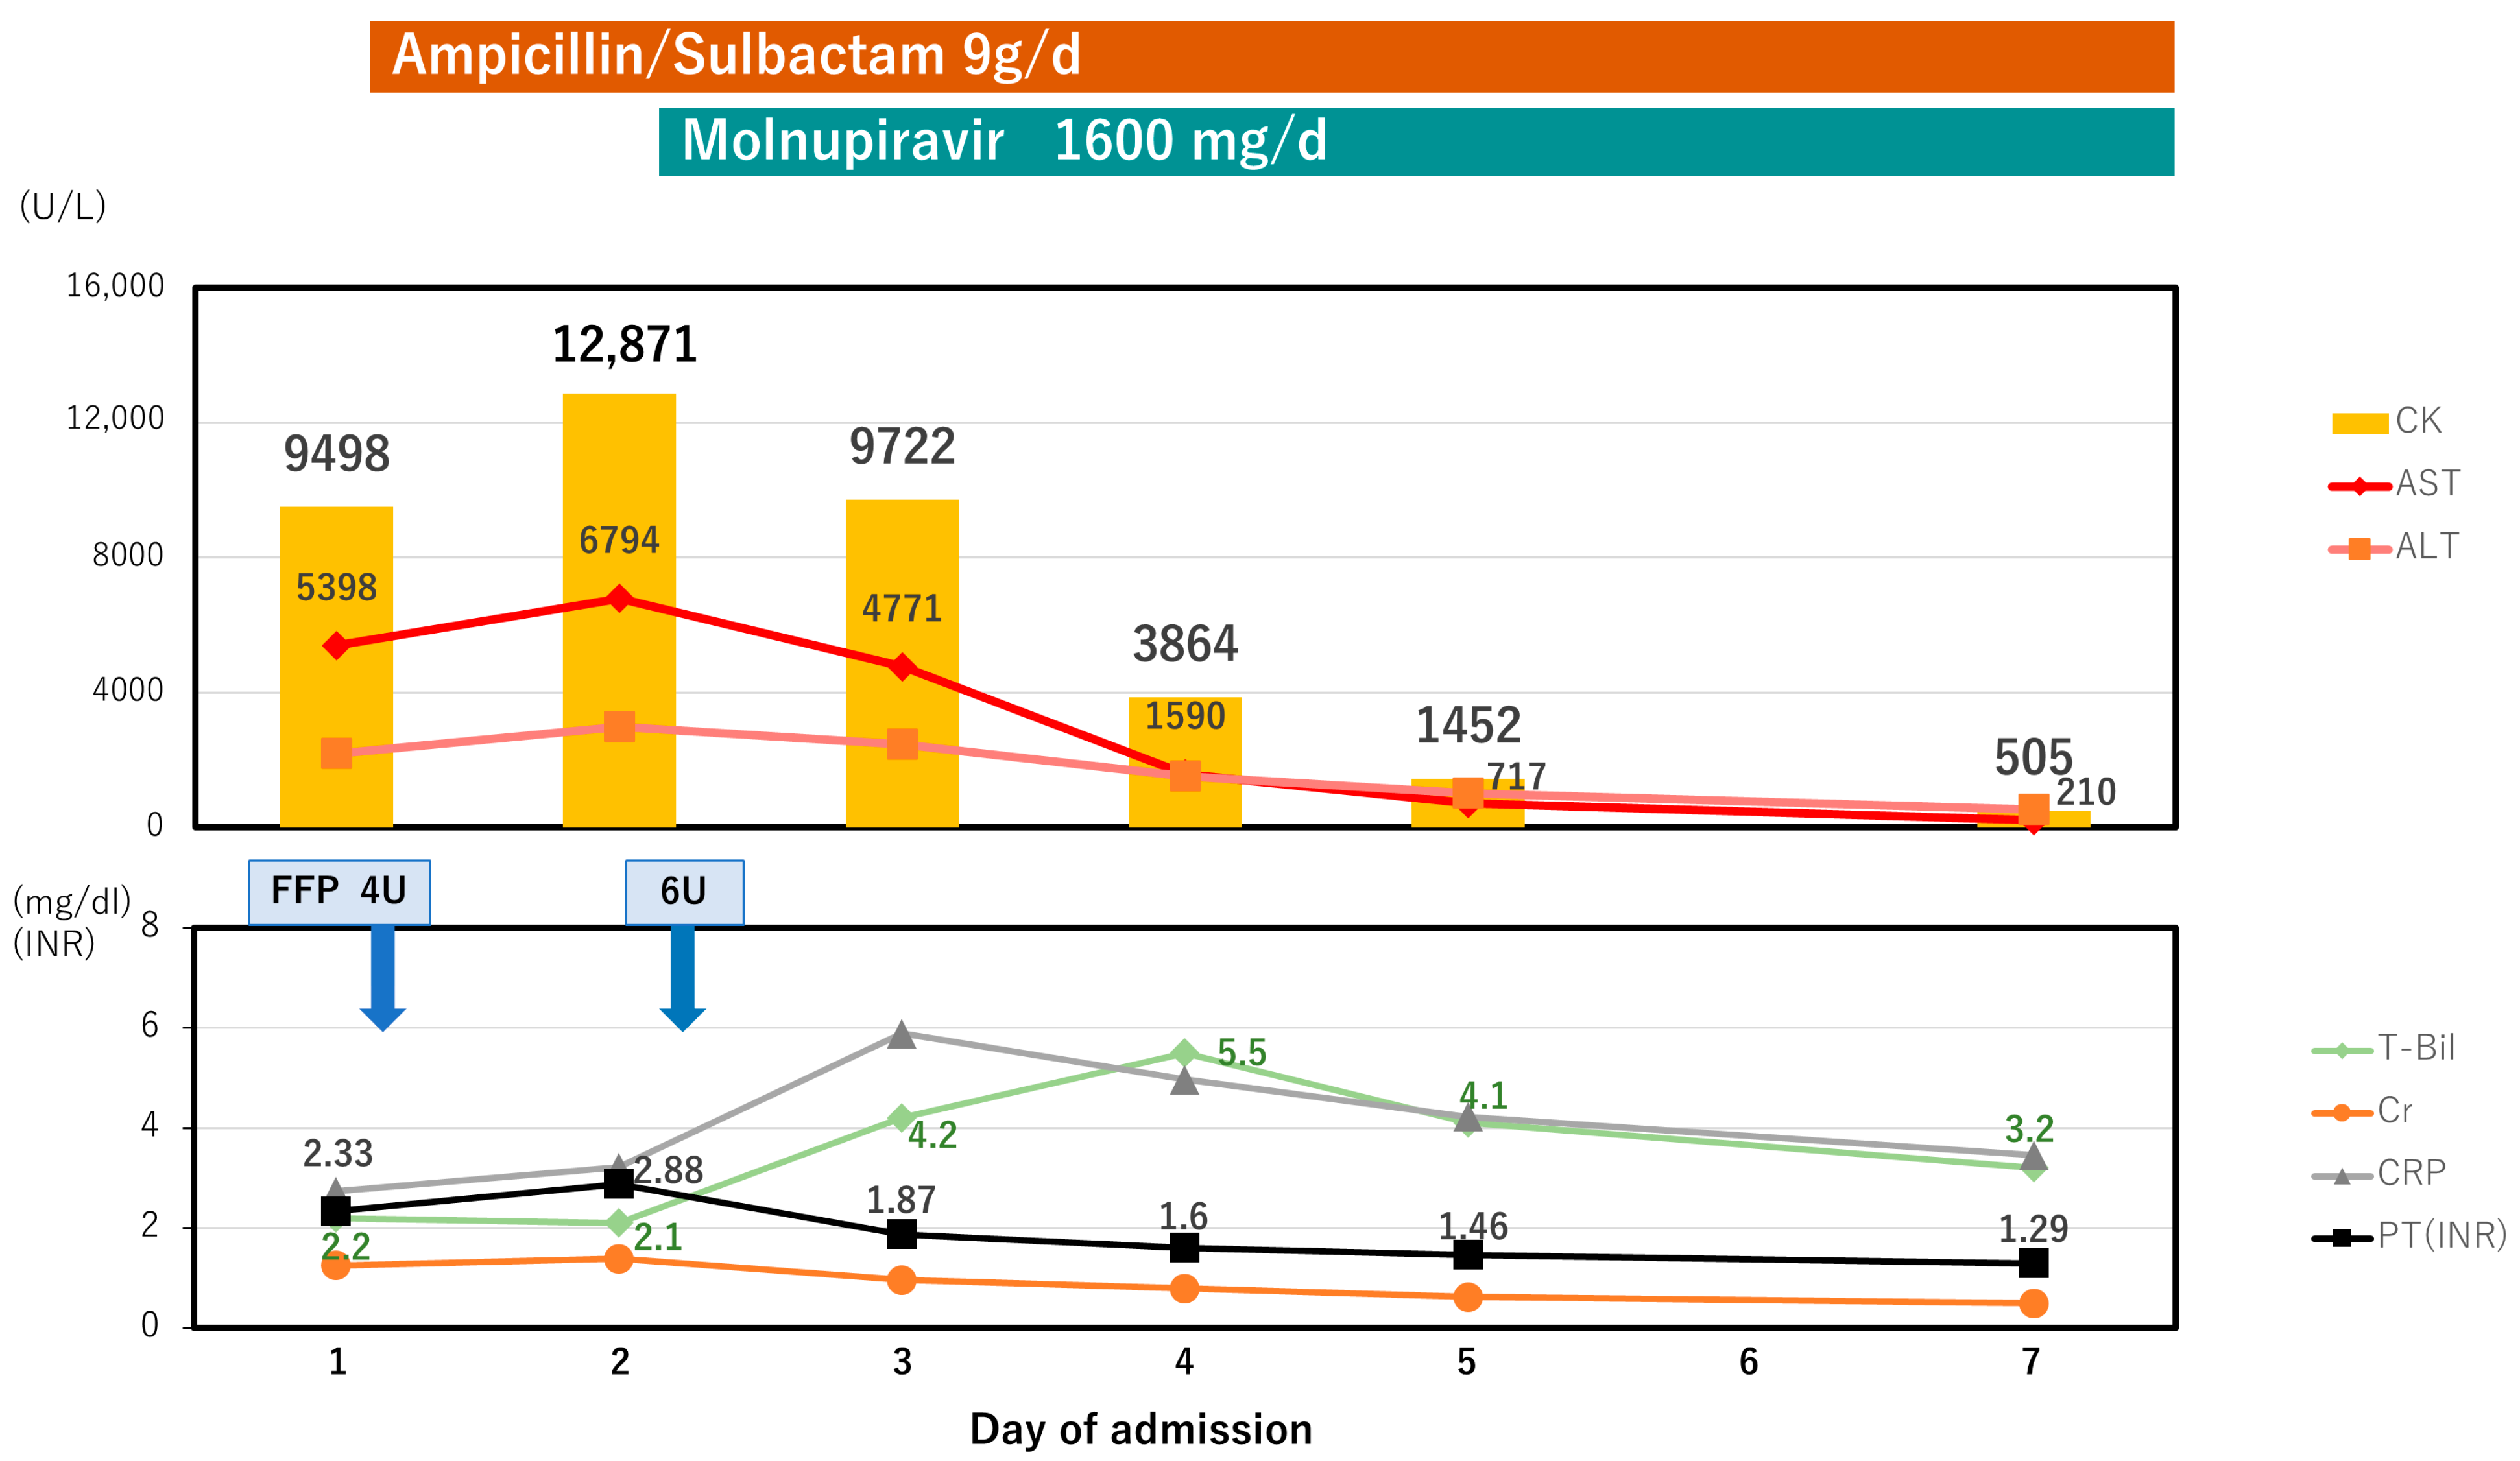

2. Case Presentation